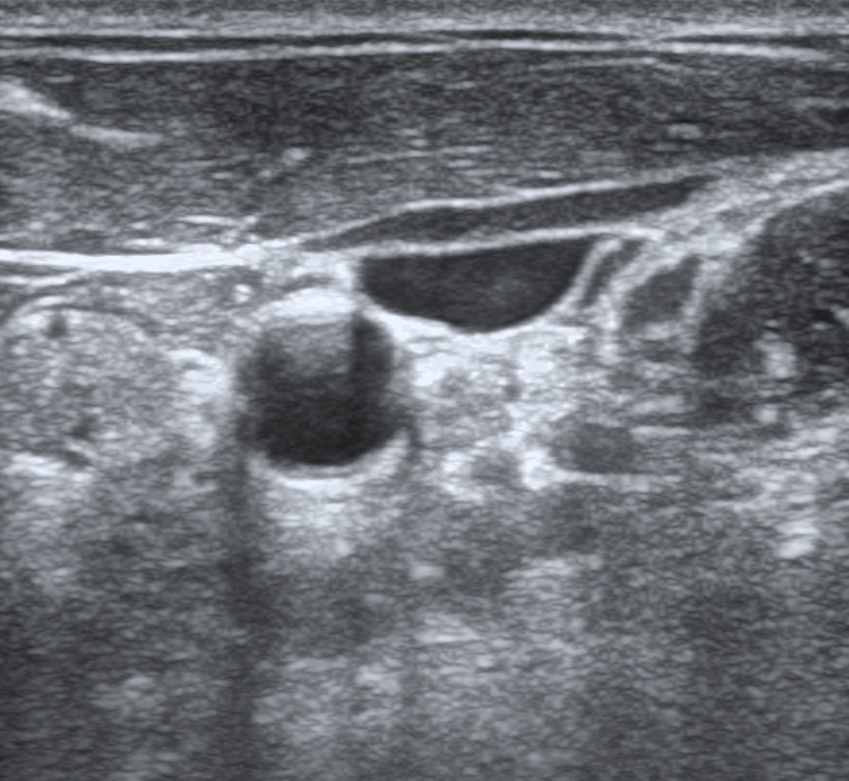

Thyroid

This scan shows the right lobe of the thyroid. The thyroid isthmus and a hyperechoic cartilaginous ring of the trachea is seen medial and anterior to the right thyroid lobe. The common carotid artery is seen pulsating medial to the right thyroid lobe.

This is a scan of the left carotid sheath. The sternocleidomastoid is overlying the internal jugular vein, which is collapsable. The common carotid artery is round and does not collapse with compression. The vagus nerve is medial to the carotid and posterior to the IJ.